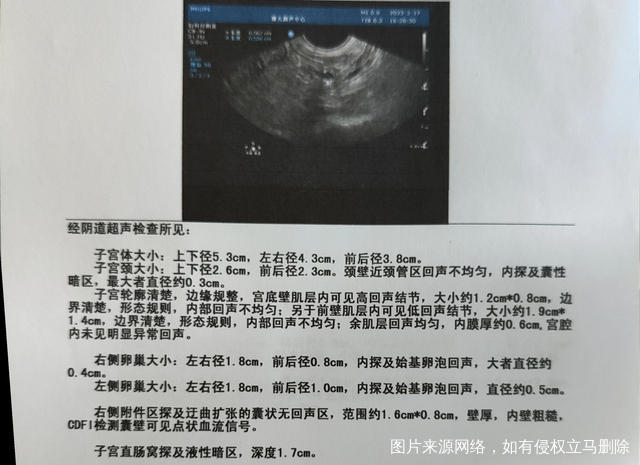

医生好!图中是月经第三天做的阴超,麻烦帮看下肌瘤多大?有几个基础卵泡?有没有其他问题?谢谢了!